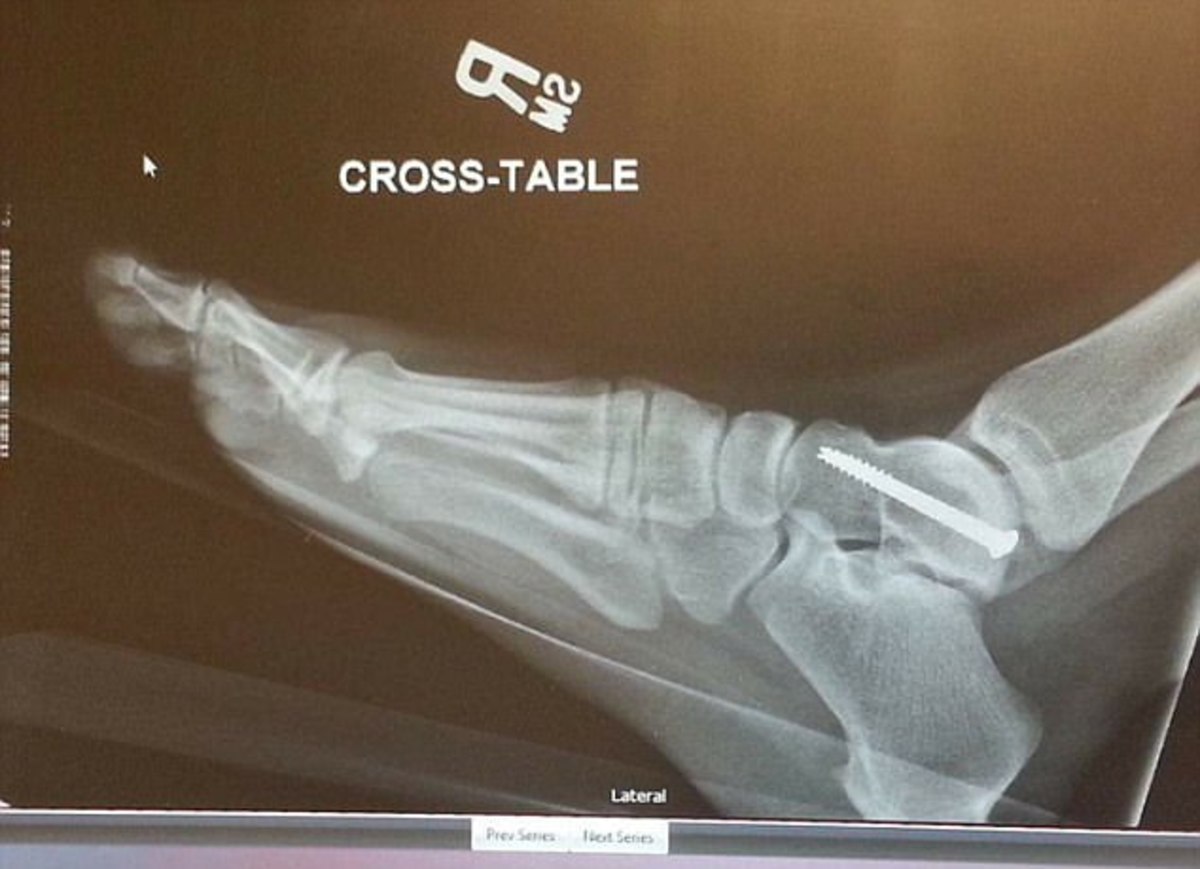

Ο αερόσακος «απαιτεί» σεβασμό, αλλιώς μπορεί να πάθετε ό,τι και και 33χρονη μητέρα τριών παιδιών, όταν, ως συνοδηγός στο αυτοκίνητο της οικογένειας που οδηγούσε ο σύζυγός της, τραυματίστηκε επειδή ακριβώς δεν… σεβάστηκε τον αερόσακο.

Η 33χρονη Audra Tatum καθόταν πάντα στο κάθισμα του συνοδηγού με το δεξί του πόδι πάνω από το αριστερό σε στάση «σταυροπόδι», παρά τις διαμαρτυρίες του συζύγου της που την προειδοποιούσε για τον κίνδυνο από τον αερόσακο.

Πριν δύο χρόνια, καθώς επέστρεφαν στο σπίτι τους, ένα αυτοκίνητο πετάχτηκε μπροστά τους και είχαν μια ελαφριά (για τις συνθήκες) πλαγιομετωπική σύγκρουση.